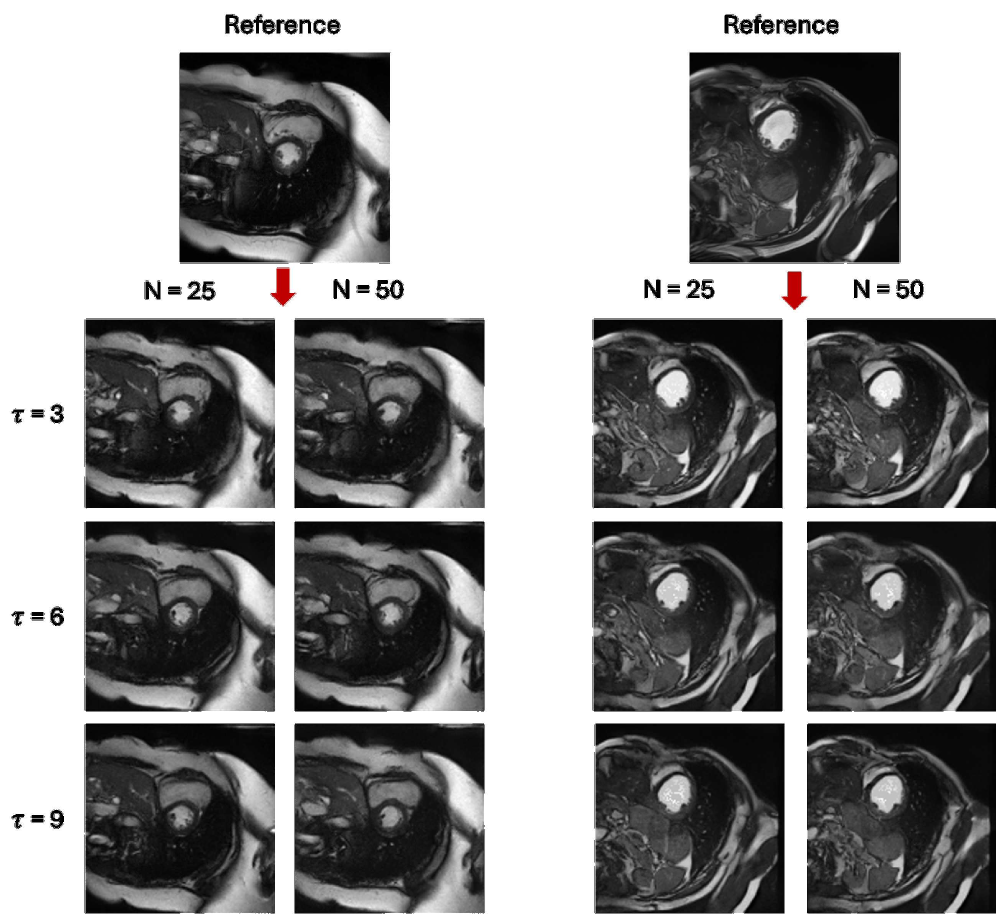

Refer to caption

Figure 3: Image synthesis using various scaling factor DD and diffusion range NN with fixed τ=6\tau=6. As DD increases, more semantic information lost (yellow \rightarrow green region).

Synthetic cardiac MR images (Fig. 4 and Fig. 4) closely resembled their respective reference image with good reconstruction on the three important regions of interest (LV, RV, MYO). With different refinement scale for image adaptation, the cardiac MR images had different level of reconstruction, highlighting a controllable trade-off between introducing novel synthetic structures and preserving reference anatomy (Fig. 5). Visual assessment revealed occasional white artifacts in the background of the generated images, likely caused by residual noise retained during the reverse process. Nevertheless, the overall anatomical structures remained well-preserved, even in the presence of a limited dataset. While diffusion models are traditionally considered data-hungry, our results suggest that structural fidelity can be maintained with constrained data availability.